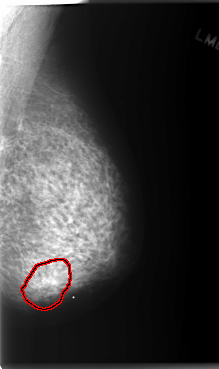

C_0148_1.LEFT_MLO

LEFT_MLO LINES 5896 PIXELS_PER_LINE 3496 BITS_PER_PIXEL 12 RESOLUTION 50 OVERLAY

FILE: C_0148_1.LEFT_MLO.OVERLAY

TOTAL_ABNORMALITIES 1

ABNORMALITY 1

LESION_TYPE MASS SHAPE LOBULATED MARGINS ILL_DEFINED

ASSESSMENT 4

SUBTLETY 1

PATHOLOGY MALIGNANT

TOTAL_OUTLINES 1

BOUNDARY